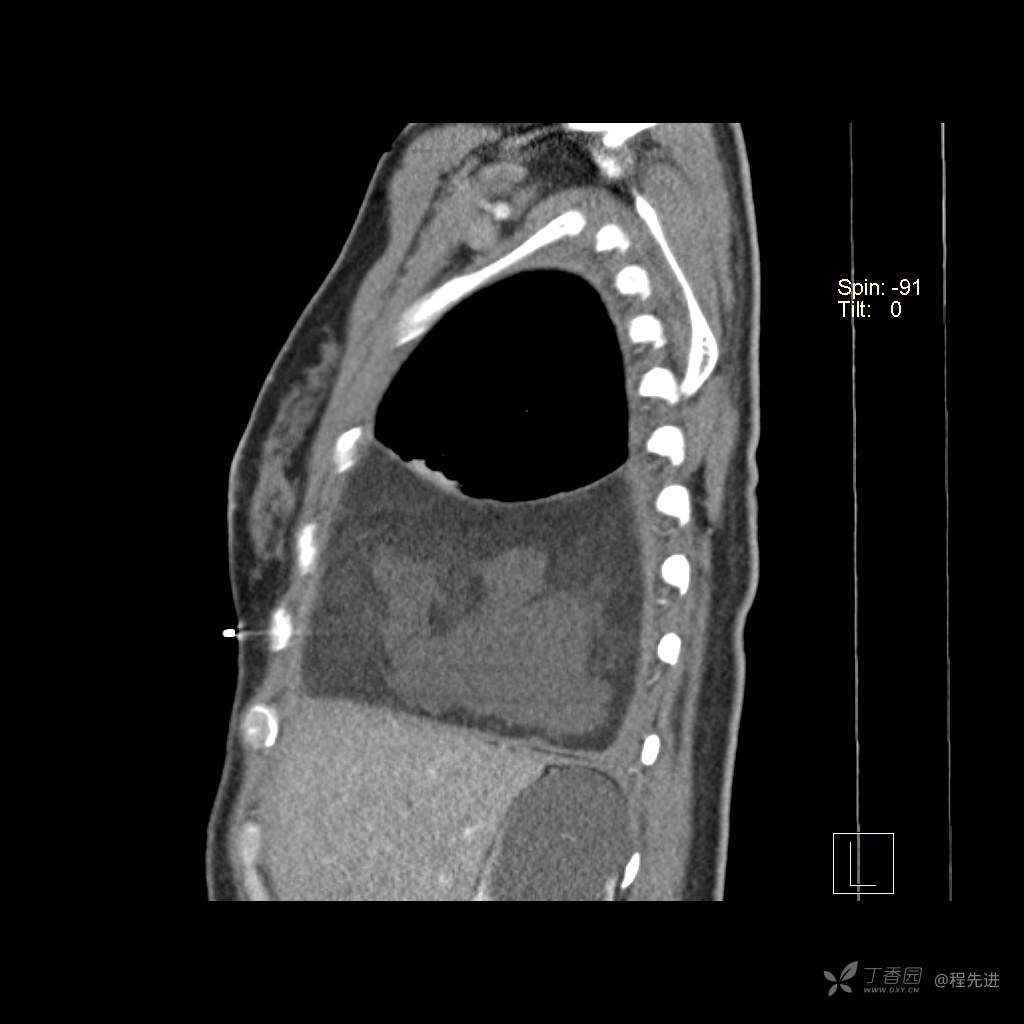

患者性别:女

患者年龄:51岁

简要病史:胸闷半年